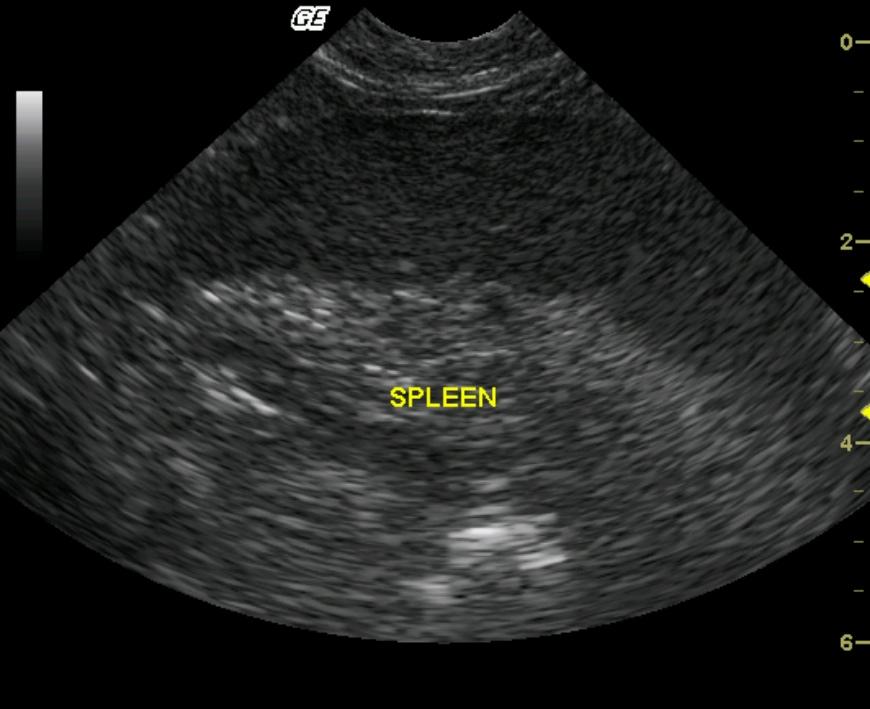

A 7-year-old F intact DSH was presented for the evaluation of dyspnea. The physical exam revealed muffled heart sounds and a thoracocentesis was performed bilaterally. One hundred milliliters (ml) of fluid was obtained from the right hemithorax and 35 ml from the left. Fluid analysis revealed cellularity to be moderate to high and RBC 100,000. Blood chemistry was performed and revealed the following abnormalities: CK 1359, albumin 3.4 g/l, direct bilirubin 0.2, and glucose 158 mg/dl.